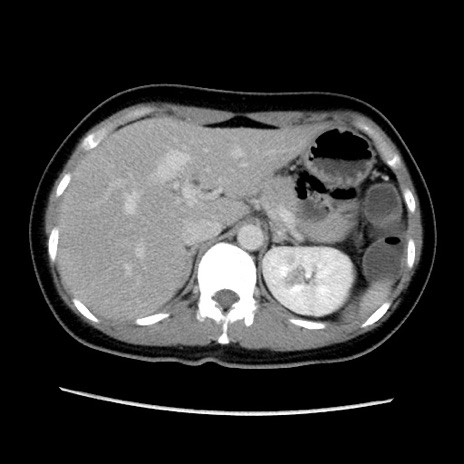

症例39(横断像)

【症例】40歳代女性

【主訴】上下腹部痛

【現病歴】2日目から下腹部痛あり。夜間は痛みで眠れなかった。昨日より上腹部痛と下痢が出現。臥位で痛みは軽快したため、休んでいた。本日になって臥位でも立位でも痛みが強くなってきたため救急要請。

【既往歴】子宮内膜症

【身体所見】部:平坦・軟、左上下腹部に圧痛あり、反跳痛あり。

【データ】WBC 21800、CRP 26.78